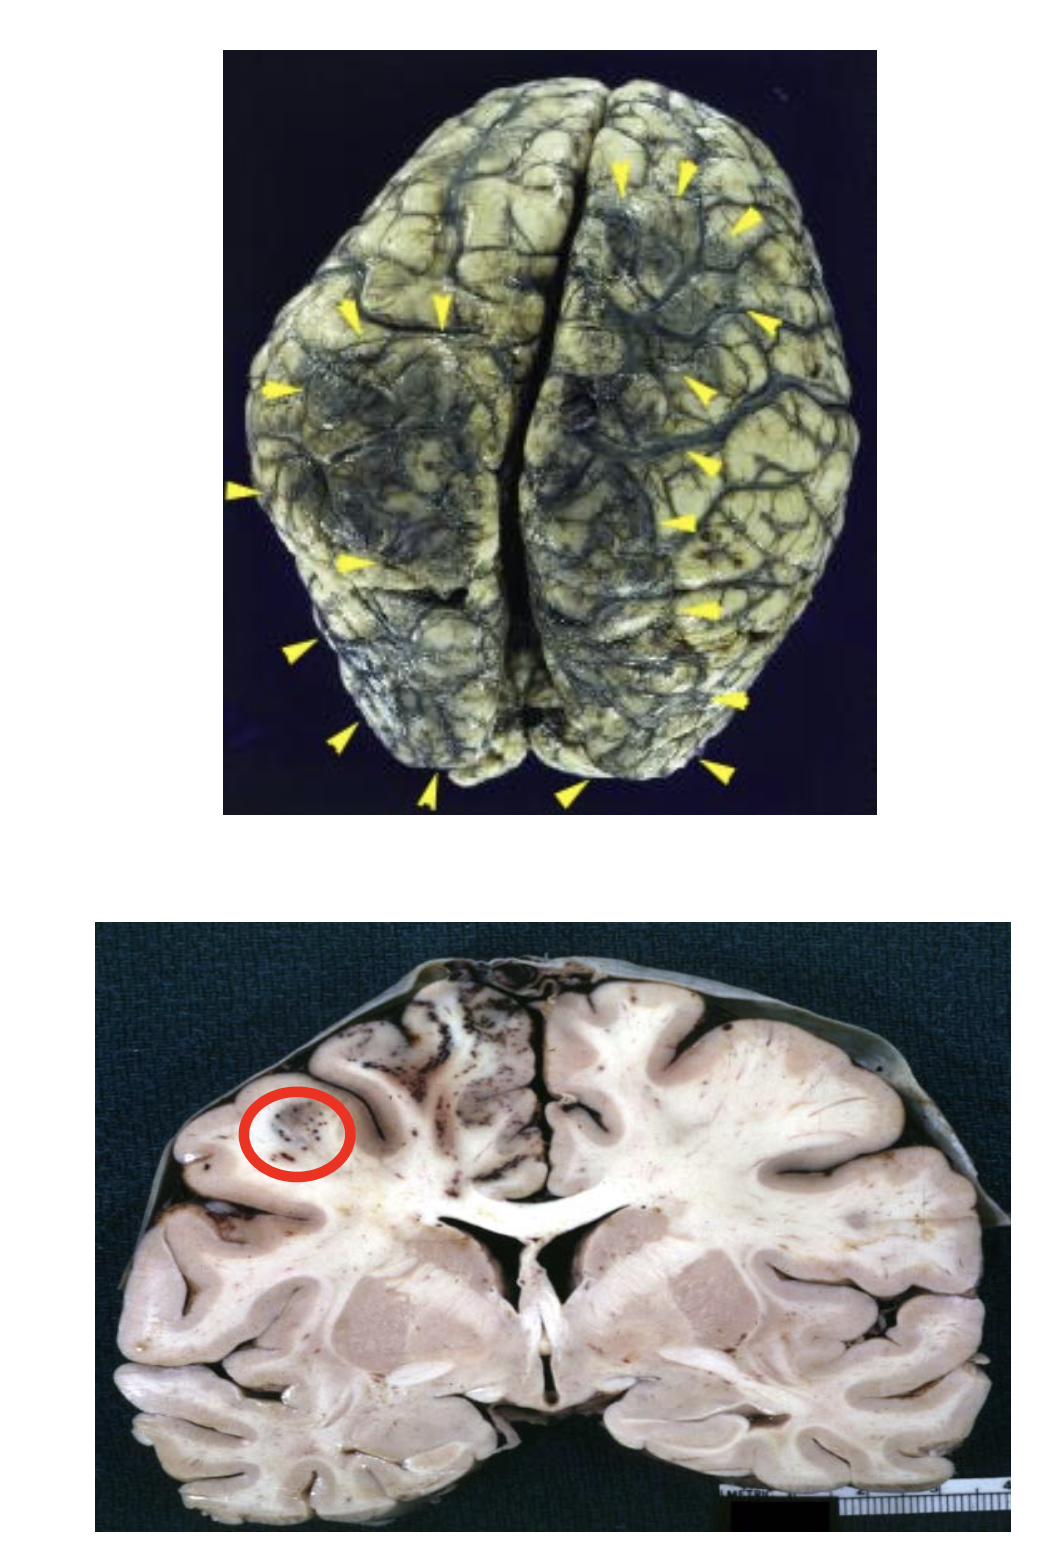

Venous sinus thrombosis

Venous congestion over the convexities (yellow arrowheads) with parietal petechial hemorrhages (circle).

Associated with: Post-partum, dehydration, hypercoagulable states, adjacent inflammation (e.g., mastoiditis).